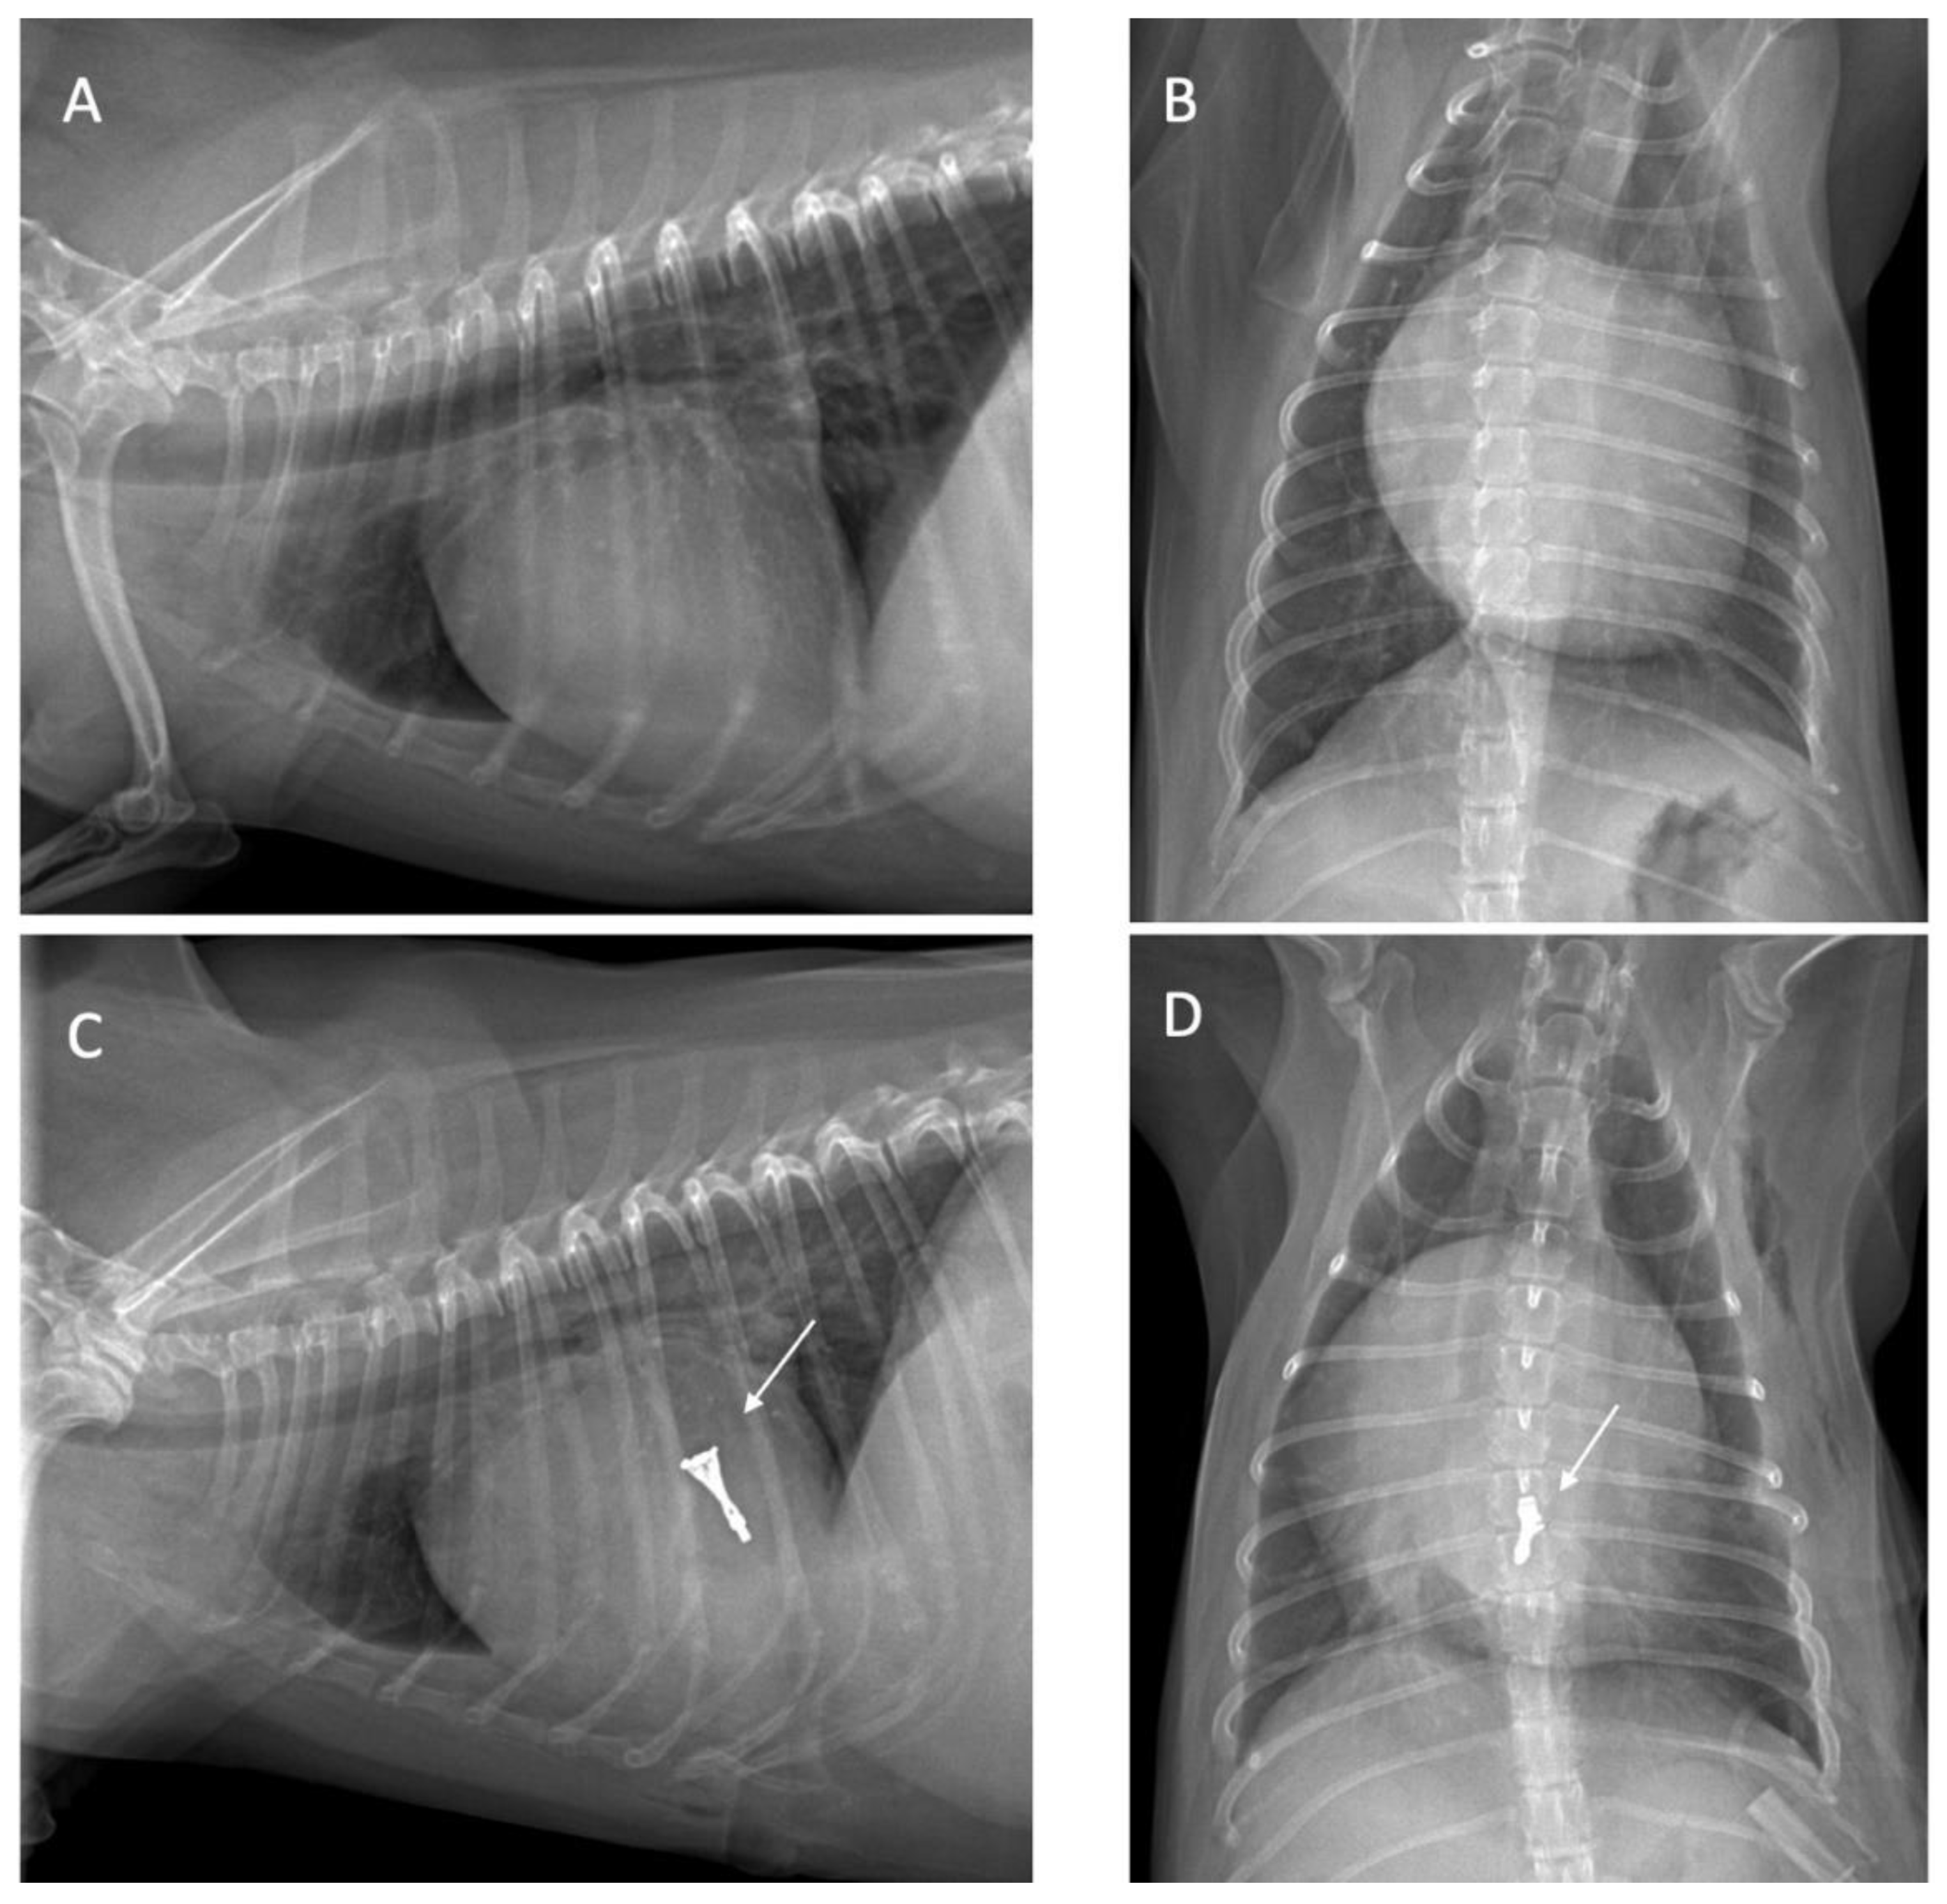

Thoracic Radiography

| Vertebral heart size (VHS) [29] | 11.2 | 11.5 | 12 | 10.5 | 11.1 | ||||

| Vertebral left atrial size (VLAS) [29] | 2.5 | 2.9 | 3.1 | 3 | 2.1 | ||||